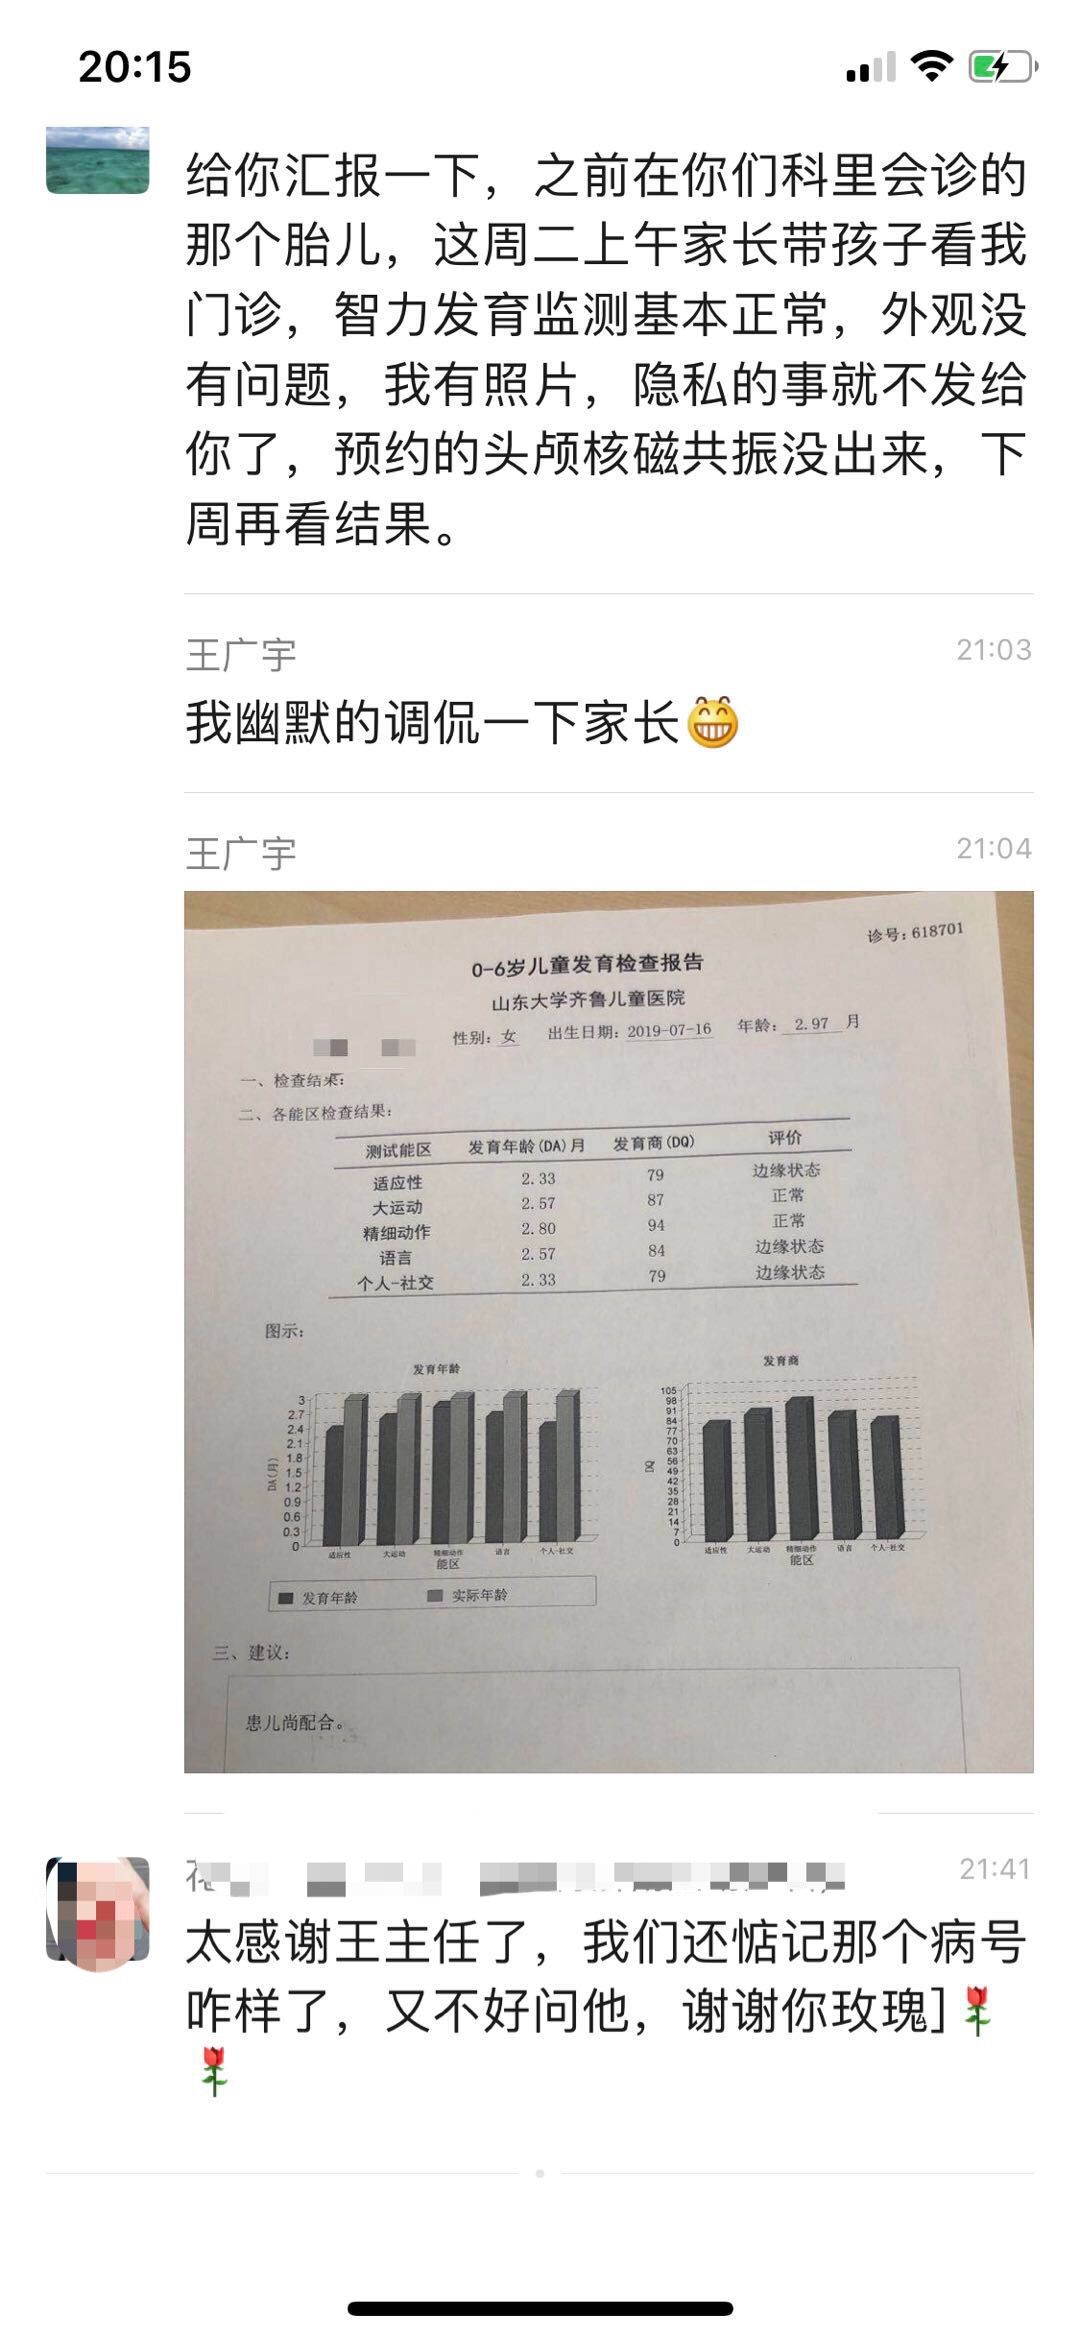

给产科医生反馈宝宝生后随诊情况